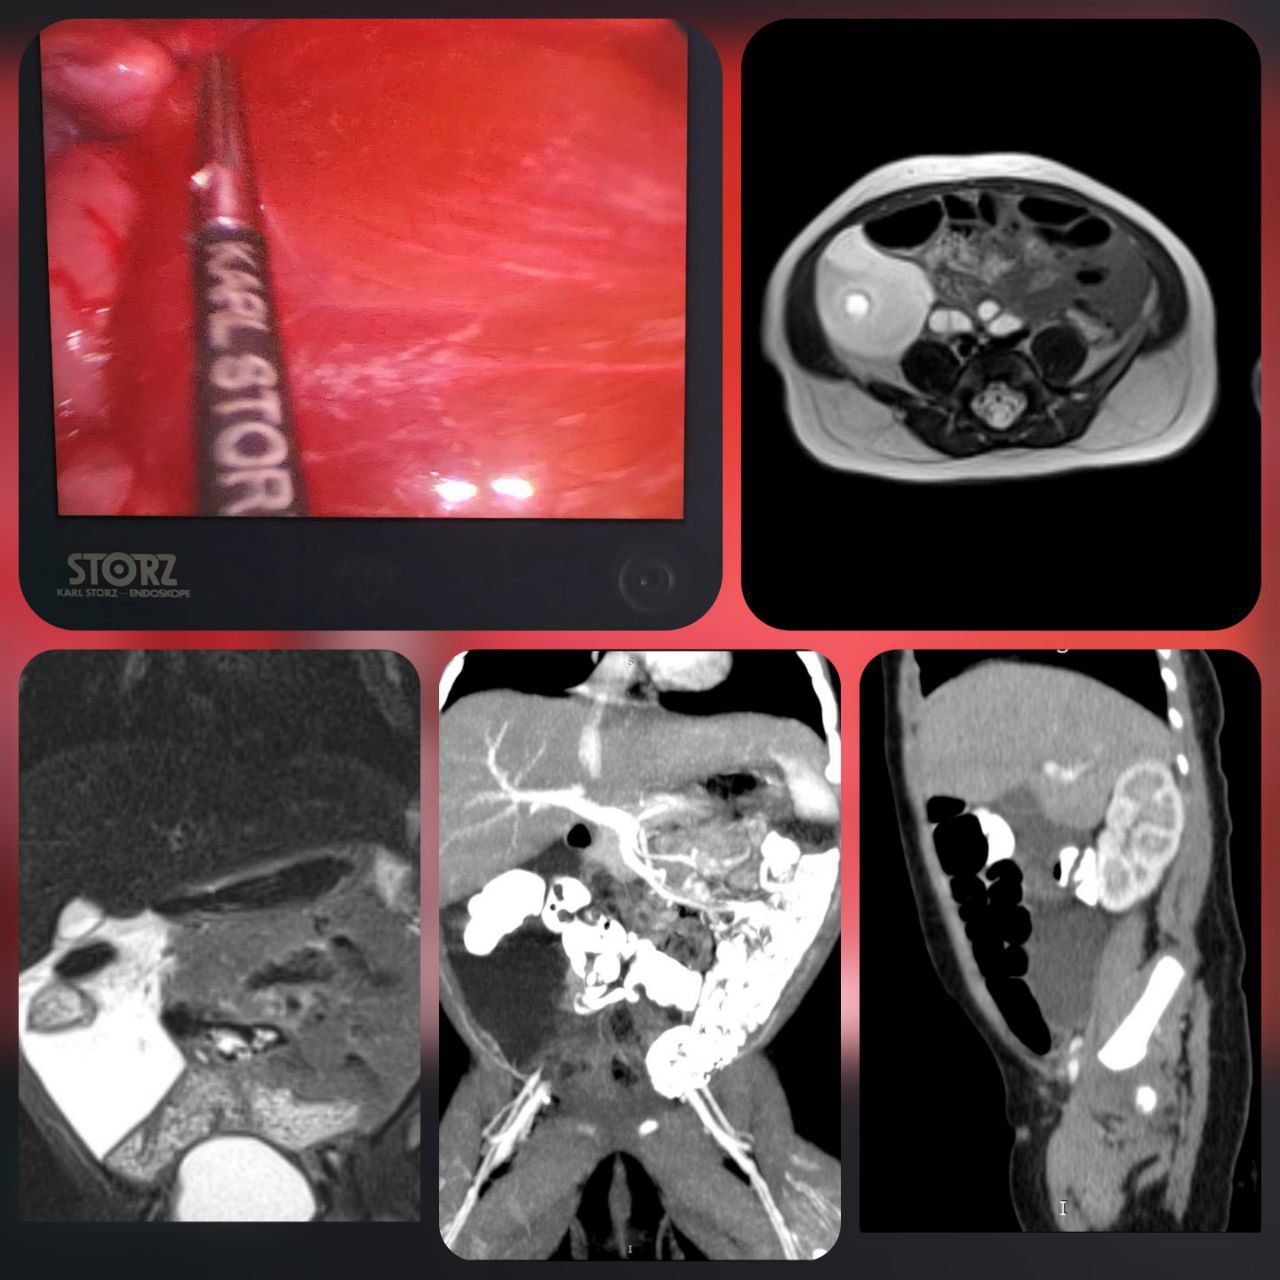

Ребенок был экстренно госпитализирован в отделение хирургии детей раннего возраста с жалобами на крупное кистозное образование в брюшной полости, которое было выявлено ещё во время внутриутробного ультразвукового исследования.

Специалисты отделения после комплексного обследования подтвердили редчайшую аномалию развития лимфатических сосудов, локализованную в брыжейке толстой кишки. Подобные случаи встречаются крайне редко – примерно в 4 на 100 000 госпитализаций, и чаще всего образования обнаруживаются в области шеи или подмышечных впадин. Лечение таких патологий сопряжено с высоким риском серьёзных осложнений, включая воспаления, перфорации и лимфоистечения.

Малоинвазивная лапароскопическая операция была выполнена командой хирургов ХДРВ – заведующей отделением, к.м.н. Марией Зыковой и врачом-детским хирургом Буй Вьет Анхом. В ходе вмешательства лимфатическая мальформация была успешно удалена с максимальным сохранением сосудов брыжейки толстого кишечника. Ключевым моментом стало использование препарата «Лимфоблок» для обработки внутренней поверхности лимфатических кист. Этот специальный раствор формирует полимерное покрытие, препятствующее повторному образованию лимфы, что значительно снижает риск рецидива заболевания.